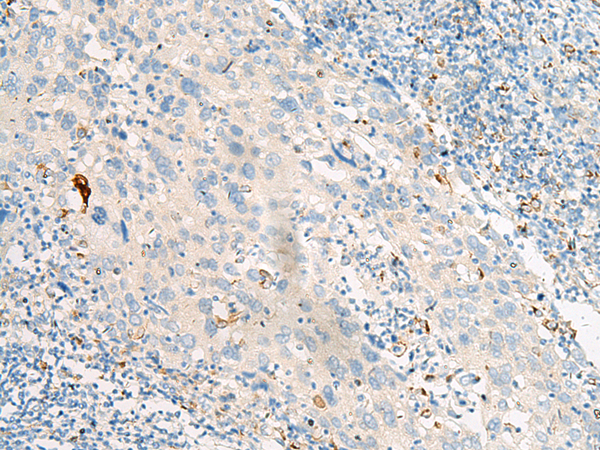

分类: 科研抗体货号: P06593别名: GPCR12; GPCR21; PPP1R84应用: IHC反应种属: Human, Mouse, Rat